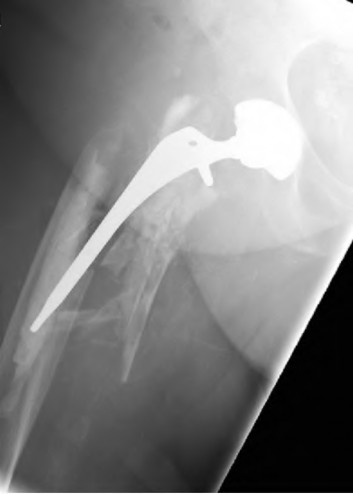

A 72-year-old female falls and sustains a periprosthetic femur fracture around her cementless total hip arthroplasty. Radiographs reveal a fracture extending just distal to the tip of the stem. The stem is radiographically loose, but there is excellent proximal and distal bone stock. According to the Vancouver classification, what is the fracture type and the recommended surgical treatment?